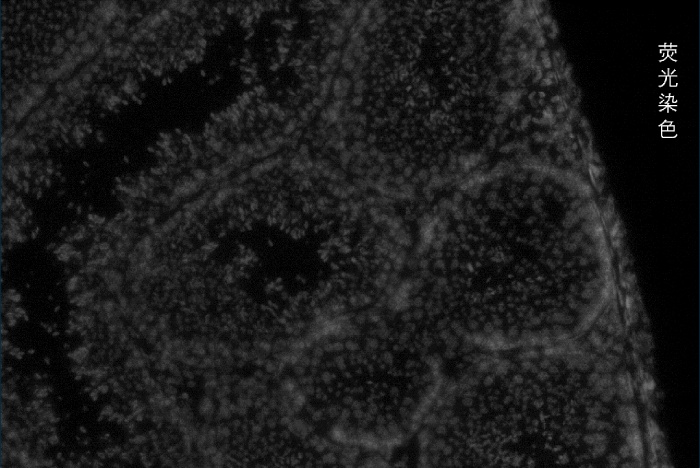

百創(chuàng)智造基于S系列空間芯片的底層設計,可以得到完全沒有錯誤的原片熒光圖像以及H&E圖像且與芯片完全對齊?;跓晒膺M行細胞核的定位刻畫細胞核的邊界;基于HE的校準輔助刻畫細胞的邊界,通過邊界信息映射到芯片上,提取相應位置的測序數(shù)據(jù),實現(xiàn)精準的單細胞分割。

2.原片熒光染色+原片H&E染色+原片空間測序相結合技術:既可以進行表達芯片H&E染色,又同時可以再表達芯片上進行熒光染色,保證細胞分割更準確。

劉總表示:若是客戶想要獲得完整的組織形態(tài)學圖片,建議先進行原片熒光染色獲得較清晰的細胞輪廓,再進行H&E染色獲得較完整的組織形態(tài)學圖片。若是細胞的組織形態(tài)學圖片已經搞清楚了,可以直接原片熒光染色,不需要H&E染色。